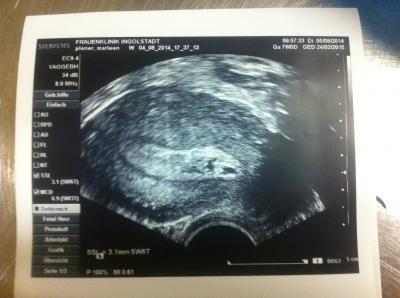

Ein weiteres Bild!

Naja, ob das jetzt ein Hämatom ist oder was auch immer, irgendwas wird es schon sein. Ich hoffe nur, dass mein kleiner Krümel nun endlich wächst und die OP auchngut überstanden hat! Ich danke euch allen; die an mich und meinem Krümel glauben und mir immer die Daumen drücken. laut Berechnungen auf dem US Gerät bin ich 5+3 oder 5+6 also 6.Ssw.

Nur mit dem erkennen tue ich mich schwer. kann eine von euch was gutes erkennen?

Das schwarze ausserhalb der GBM ist Flüßigkeit von der OP, die mir auch noch Schmerzen macht. Aber ich will keine Medikamente mehr nehmen. Innen das weiße, weiß ich leider Nicht ob das Blut ist. Aber das hätte ja die Ärztin gesagt. Ich bin nur noch diese Nacht im Krankenhaus, werd morgen entlasseN, wenn alles gut ist. Morgen wird der HCG nochmal kontrOlliert. hoffentlich fällt der Wert gut aus. Ich werd dann mal versuchen zu schlafen. Gute Nacht euch allen!

Also das sieht doch gut aus.Blut kann man nicht sehen... es wäre schwarz zu erkennen... und ich meine man kann viel sehen in der Fruchthöhle....den Dottersack und wenn ich mich nicht täusche auch das kleine würmchen in der ecke... Deine Geschichte ist wirklich unglaublich.... Ich drücke dir weiter die Daumen !!! Und denk ganz viel an dich und dein kleinen tapferen Krümel!